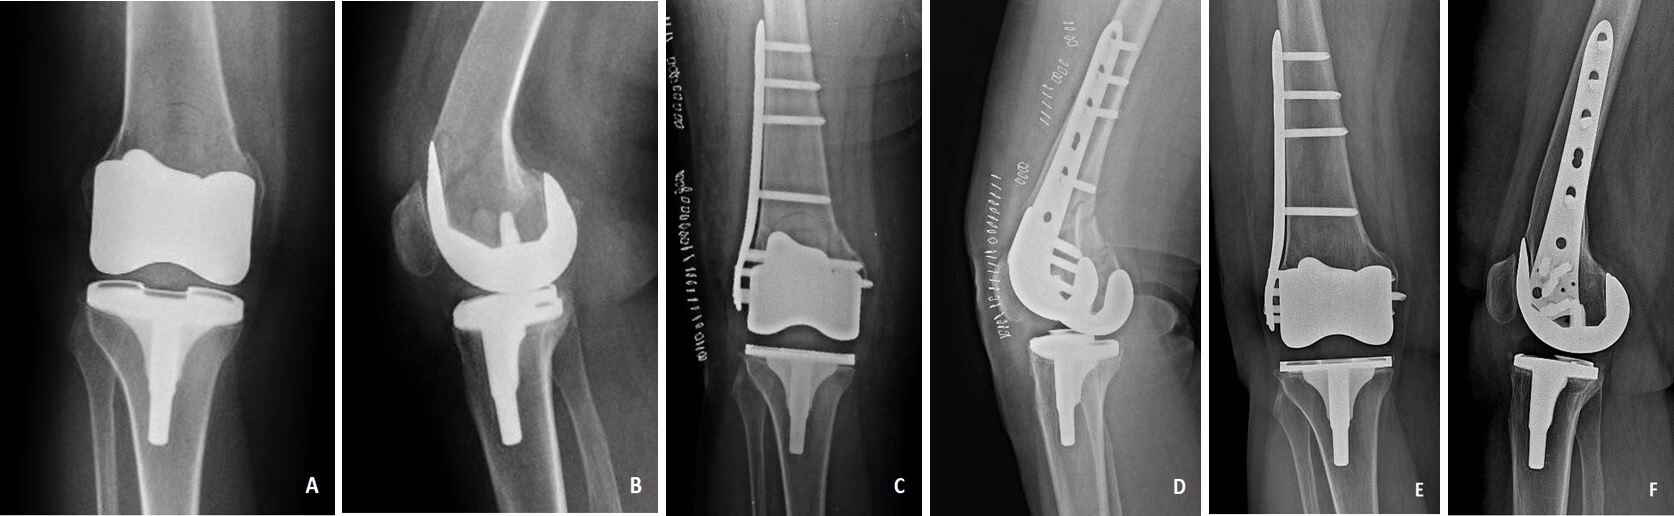

En Særlig Komplikation: Brud omkring Protesen

En mindre hyppig, men alvorlig komplikation er et knoglebrud omkring knæprotesen (periprotetisk fraktur). Dette sker oftest i lårbenet lige over protesen og er typisk forårsaget af et fald. Ældre patienter med svagere knogler (osteoporose) er i højere risiko. Et sådant brud er en alvorlig skade, der kræver øjeblikkelig hospitalsindlæggelse. Behandlingen er næsten altid kirurgisk og afhænger af bruddets placering og kompleksitet. Mulighederne inkluderer:

- Plade og skruer: Bruddet stabiliseres med en metalplade og skruer, der fastgøres til knoglen.

- Marvsøm: Et langt metalsøm føres ned gennem lårbenets marvhule for at stabilisere bruddet indefra.

- Revisionsoperation: I tilfælde, hvor bruddet er tæt på protesen, eller hvis protesen er blevet løs, kan det være nødvendigt at fjerne den gamle protese og erstatte den med en større revisionsprotese, der også erstatter den brækkede del af knoglen.